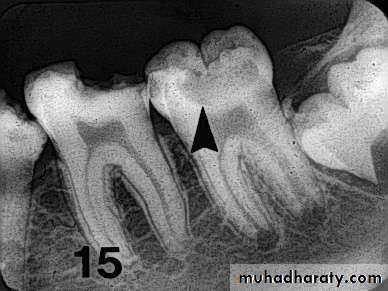

Advanced proximal lesions

Incipient proximal lesionsModerate proximal lesions

OTHER RADIOGRAPHIC SHADOWS

Radiolucent Cervical Burn out:- Evident at the neck of tooth

well demarcated above by

enamel cap& below by alveolar

bone level

- It is triangular in shape

being less apparent at the center

of tooth

-good alveolar bone height

will enhance cervical burn-out